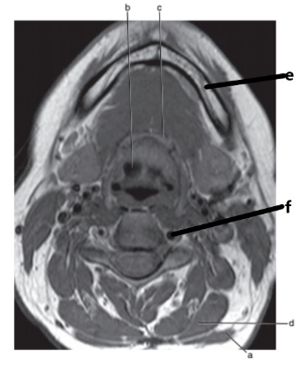

What imaging plane is this ?

transverse

What anatomy is letter b ?

Epiglottis

What is letter f ?

Spinal cord

Masseter muscle

What is letter e ?

Mandible

What is letter h ?

Internal carotid artery

Common carotid artery